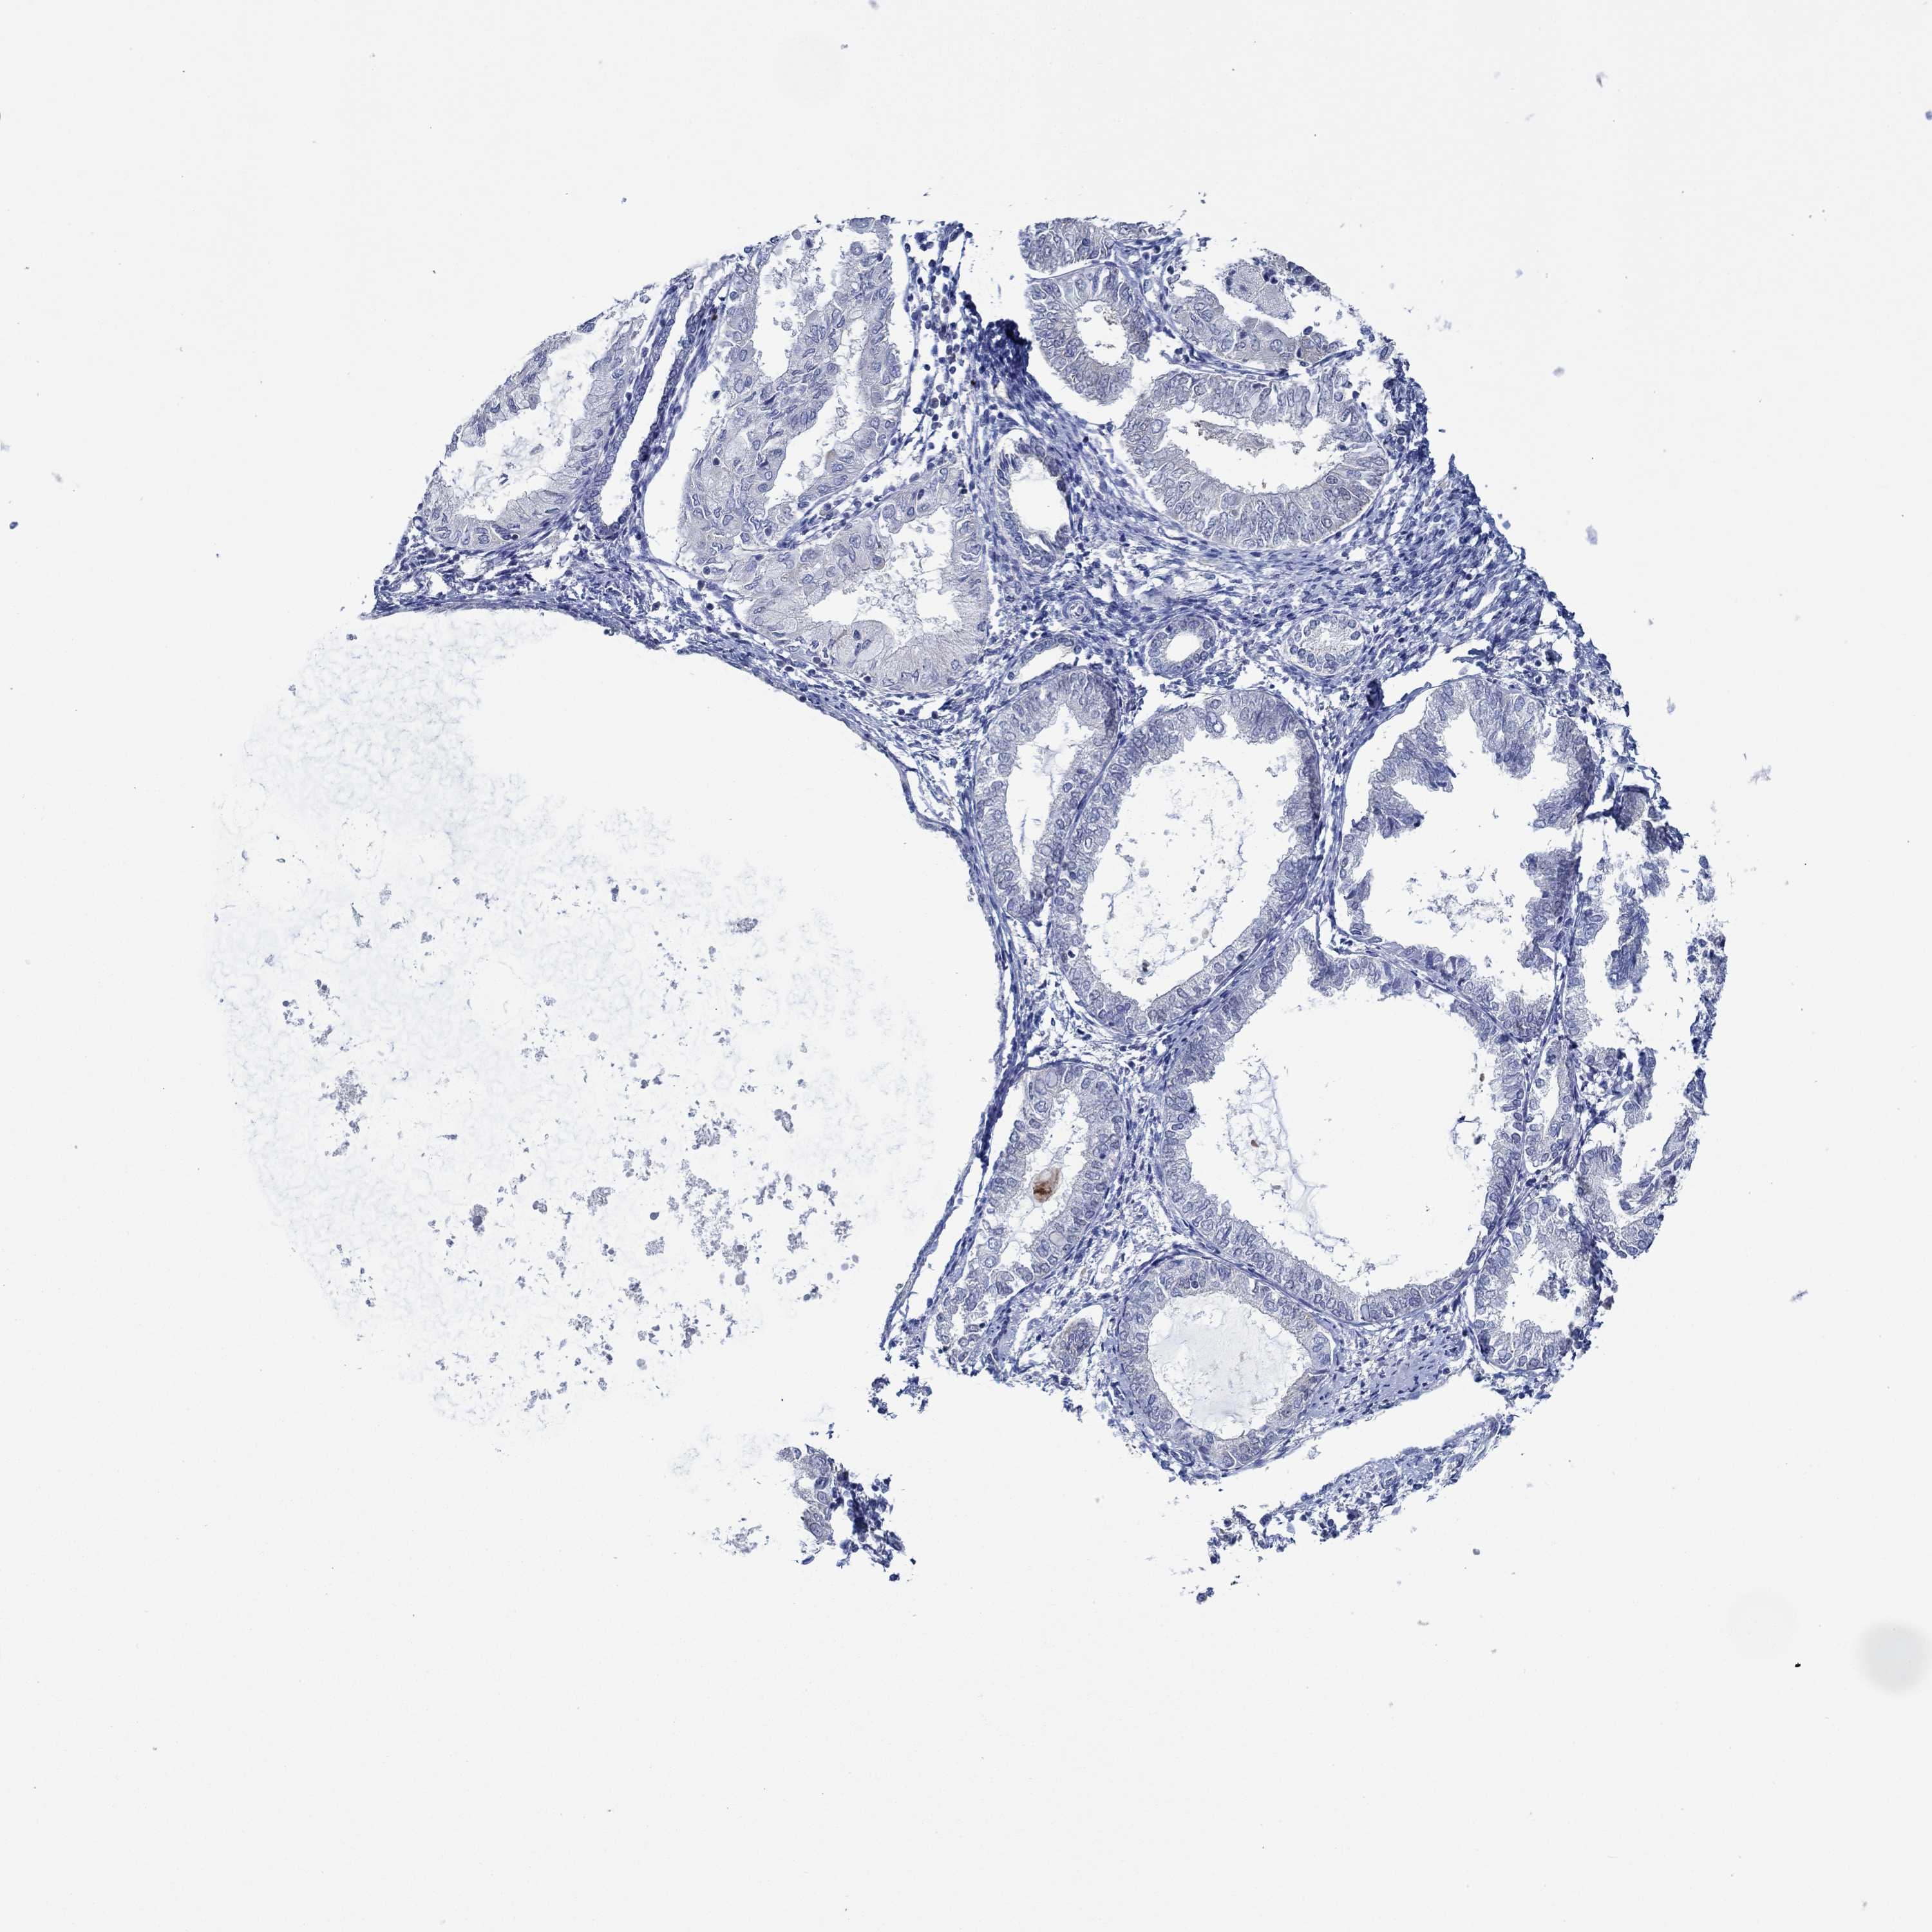

ENDOMETRIAL CANCER - Protein expressioni

A mouse-over function shows sample information and annotation data. Click on an image to view it in a full screen mode. Samples can be filtered based on level of antibody staining by selecting one or several of the following categories: high, medium, low and not detected. The assay and annotation is described here.

Note that samples used for immunohistochemistry by the Human Protein Atlas do not correspond to samples in the TCGA dataset.

Antibody stainingi

Antibody staining in the annotated cell types in the current human tissue is reported as not detected, low, medium, or high, based on conventional immunohistochemistry profiling in selected tissues. This score is based on the combination of the staining intensity and fraction of stained cells.

Each image is clickable and will lead to virtual microscopy that enables deeper exploration of all samples and also displays staining intensity scores, fraction scores and subcellular localization as well as patient and tissue information for each sample.

Antibody HPA067508

Antibody CAB080514

Antibody CAB080517

Staining

High

Medium

Low

Not detected

Intensity

Strong

Moderate

Weak

Negative

Quantity

>75%

75%-25%

<25%

None

Location

Nuclear

Cytoplasmic/membranous

Cytoplasmic/membranous,nuclear

Adenocarcinoma, NOS

Adenocarcinoma, metastatic, NOS